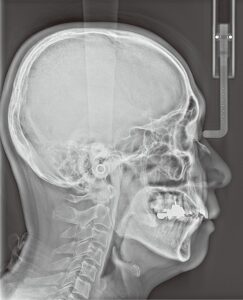

【セファロ画像(例)】

骨格と歯の位置関係を評価し、設計の根拠にします。